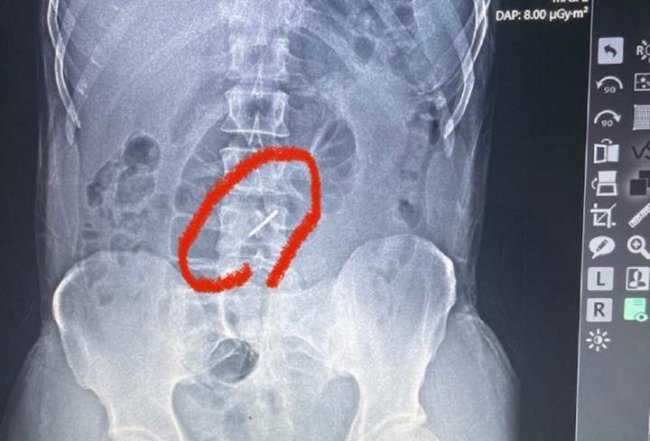

Як розповів лікар військово-польового госпіталю Тарас Кобза, коли бійця скерували на рентген, аби чітко встановити причину болю, то лікарі були шоковані побаченим на рентгенівському знімку.

"Під час обстрілу елемент касетної бомби, так звана "стрілка", потрапила у ліве підребер'я, зламала два хребці у поперековому відділі хребта і застрягла у хребті. Уламки зламаних хребців могли ушкодити нерви, судини, але, на щастя, цього не сталося. Боєць прийшов у польовий госпіталь своїми ногами і навіть не підозрював, що у його хребті застряг елемент касетної бомби", – каже Тарас Кобза.

За його словами, боєць потрапив під обстріл ще 13 липня, а до шпиталю звернувся лише на початку серпня. Він практично три тижні воював зі зламаним хребтом. Наразі бійця із зони бойових дій відправили в одну з лікарень у більш безпечний регіон, де він проходитиме лікування.